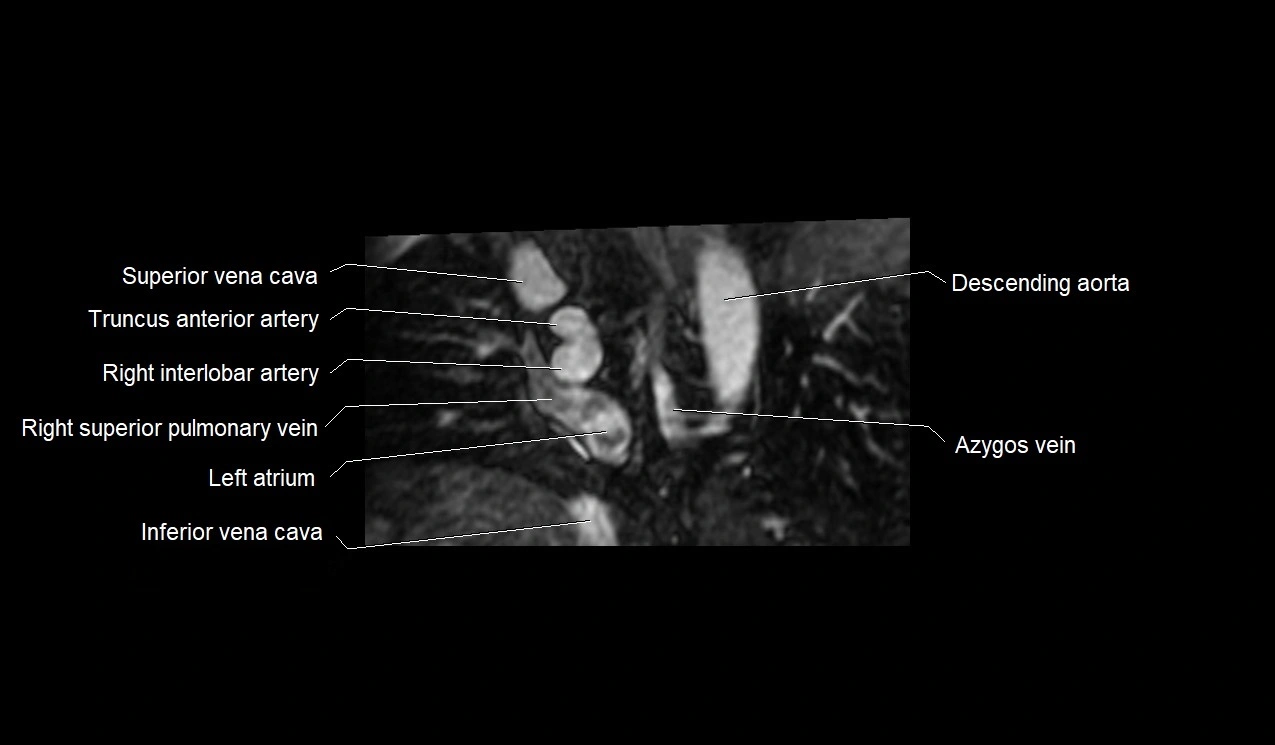

- Azygos vein

- Inferior vena cava

- Left atrium

- Right interlobar artery

- Right superior pulmonary vein

- Superior vena cava